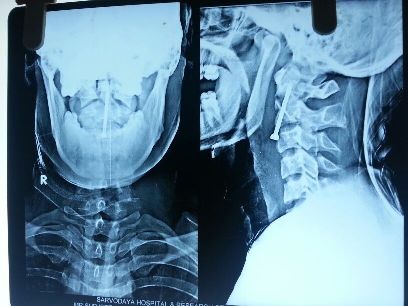

cervical

Anterior Cervical Fixation.